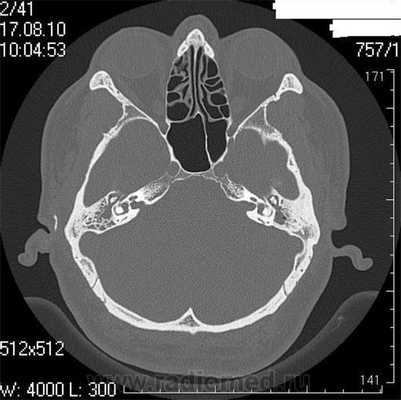

Снимок (томограмма) височных костей в осевой проекции

На КТ-снимке виден перелом пирамиды височной кости (указан стрелками)